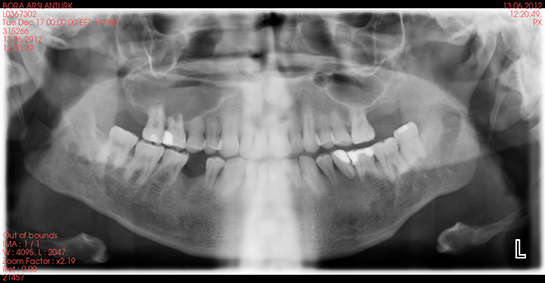

Diş Kökü İltihabının Tanısı Diş kökü iltihabının tanısı çoğunlukla diş hekimi tarafından yapılır. Tanı süreci şu adımları içerebilir: